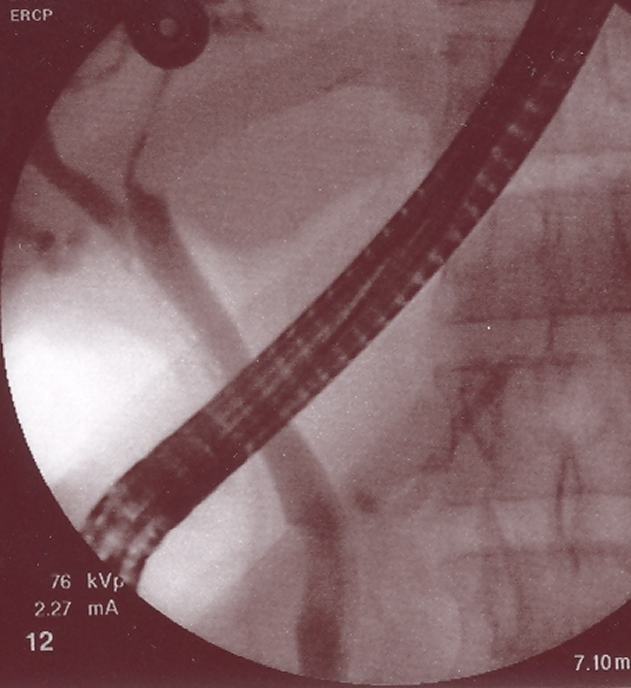

A 27-year-old Egyptian male with no significant comorbidities presented with history of episodic, recurrent abdominal pain of 4 years duration to our clinic at King Abdul Aziz specialist hospital Taif, a tertiary care centre in the western region of Saudi Arabia. Patient described pain as colicky, remaining for 1–2 hours necessitating intravenous analgesics predominantly in the upper abdomen. His abdominal pain had no reference or radiation and there was no jaundice associated with it. Patient had been admitted four times in various hospitals during this period and every time basic laboratory evaluation including liver function tests and serum amylase were within normal limits. His ultrasound examination had been within normal limits on each occasion he was hospitalized for his abdominal pain. Patient denied any high risk behavior or drug abuse. Over this period he had stable appetite and constant weight. On examination he was conscious oriented and he had stable vitals. There was no icterus, or lymphadenopathy. His systemic examination was unremarkable. Laboratory data revealed normal hemogram, normal liver function tests and his abdominal ultrasound was also within normal limits. There were no eggs or ova in his stool examination. Keeping in view recurrent biliary colics magnetic resonance cholangiopancreatography (MRCP) was done which showed a doubtful filling defect in the common bile duct but intra-hepatic biliary radicals were not dilated. There were no gall stones and the rest of the viscera were within normal limits. Endoscopic retrograde cholangiopancreatography (ERCP) was undertaken which revealed normal papilla. Selective common bile duct (CBD) canulation was done and cholangiogram revealed a filling defect in the lower end of common bile duct. There was mild dilatation of the common bile duct (Figure 1 [Fig. 1]) however, biliary radicals were not dilated. Sphincterotmy was done and CBD was sweeped with biliary balloon and a live Fasciola hepatica was seen coming out of the common bile duct (Figure 2 [Fig. 2], Figure 3 [Fig. 3]). Later using biopsy forceps the worm was taken out of duodenum and confirmation of the species, Fasciola hepatica, was made by the microbiology department of the hospital. Patient was given two tablets of triclabendazole 250 mg (manufactured by Novartis) after the procedure. Following therapeutic ERCP patient became symptom free and is attending our clinic for last 11 months now.